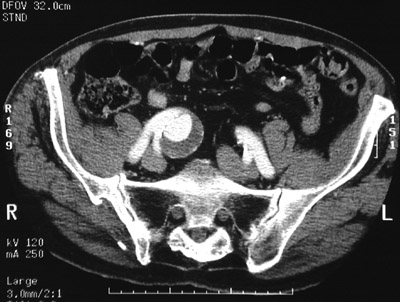

This pelvic CT scan with contrast reveals an

atherosclerotic aneurysm

involving the right common iliac artery just above its bifurcation. Note the bright contrast next to a rim of dark

mural thrombus

.